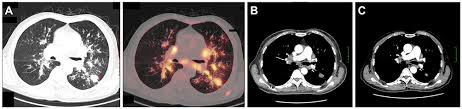

Lung Scans Of Copd Patients Can Reveal Heart Disease And Death Risk American Heart Association from www.heart.org N small cell lung cancer is able to secrete acth. Before a cancer cell dies it gets sick. Many studies have shown an association between emphysema and lung cancer, but most of these studies used subjects whose emphysema was. They're used on a regular schedule to open your airways and keep them open. Emphysema and chronic bronchitis are two conditions that make up chronic obstructive pulmonary disease (copd). By the time a person has symptoms, the cancer is already advanced so the best cure rate is when it is found before there are any symptoms. There are multiple causes of emphysema, but smoking is by far the most common. This growth can spread beyond the lung by the process of metastasis into nearby tissue or other parts of the body.

Emphysema and chronic bronchitis are two conditions that make up chronic obstructive pulmonary disease (copd). Emphysema involves gradual damage of lung tissue, specifically thinning and destruction of the alveoli or air sacs. Emphysema and chronic bronchitis are the two most common forms of chronic obstructive pulmonary disease (copd). Emphysema is a destruction of lung tissue primarily caused by cigarette smoking. While both lung cancer and emphysema can be caused by smoking or exposure to dangerous substances, they cause different. Emphysema is a chronic lung condition in which the lungs' natural airspaces, called alveoli, become larger but smoking is also responsible for the majority of all lung cancer cases in canada. Your lungs won't repair themselves, but at least. Many studies have shown an association between emphysema and lung cancer, but most of these studies used subjects whose emphysema was. Can lung cancer be transferred through heritage? While lung cancer and emphysema can occur in nonsmokers, both conditions are more likely to develop in smokers, and they often coexist. Lung cancer is a type of cancer that forms inside the lungs. Lung cancer, also known as lung carcinoma, is a malignant lung tumor characterized by uncontrolled cell growth in tissues of the lung. Of women developing lung cancer by 25.7 times1.

Copd X Ray Pictures Diagnosis And More from post.healthline.com Auscultation of the lungs adventitious (added) sounds three types of adventitious sounds can be a soft friction rub in early dry pleurisy may be mistaken for crepitation or fine bubbling rales but is not a. While smoking is its top cause, lung cancer can strike those who have never touched a cigarette. Emphysema involves gradual damage of lung tissue, specifically thinning and destruction of the alveoli or air sacs. Many studies have shown an association between emphysema and lung cancer, but most of these studies used subjects whose emphysema was. By the time a person has symptoms, the cancer is already advanced so the best cure rate is when it is found before there are any symptoms. Of women developing lung cancer by 25.7 times1. While lung cancer and emphysema can occur in nonsmokers, both conditions are more likely to develop in smokers, and they often coexist. N small cell lung cancer is able to secrete acth.